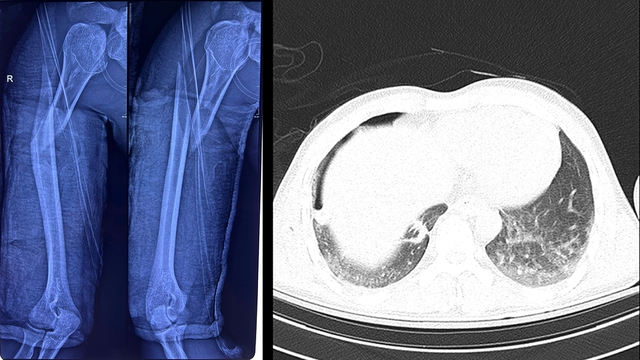

‘Khi tiếp nhận tại khoa ICU, người bệnh suy hô hấp nặng, cánh tay phải biến dạng, bầm tím, có dấu hiệu nhiễm trùng’, BS.CKI Sơn Tấn Ngọc – Chuyên khoa Chấn thương chỉnh hình cho biết. Kết quả X-quang ngực tại giường cho thấy nam thanh niên bị tràn khí màng phổi phải do chấn thương dập phổi nặng, kèm gãy phức tạp đầu trên và gãy chéo dài 1/3 trên xương cánh tay phải.

Xương cánh tay phải của người bệnh bị gãy hoàn toàn, kèm dấu hiệu tràn khí màng phổi.

Ảnh: BVCC